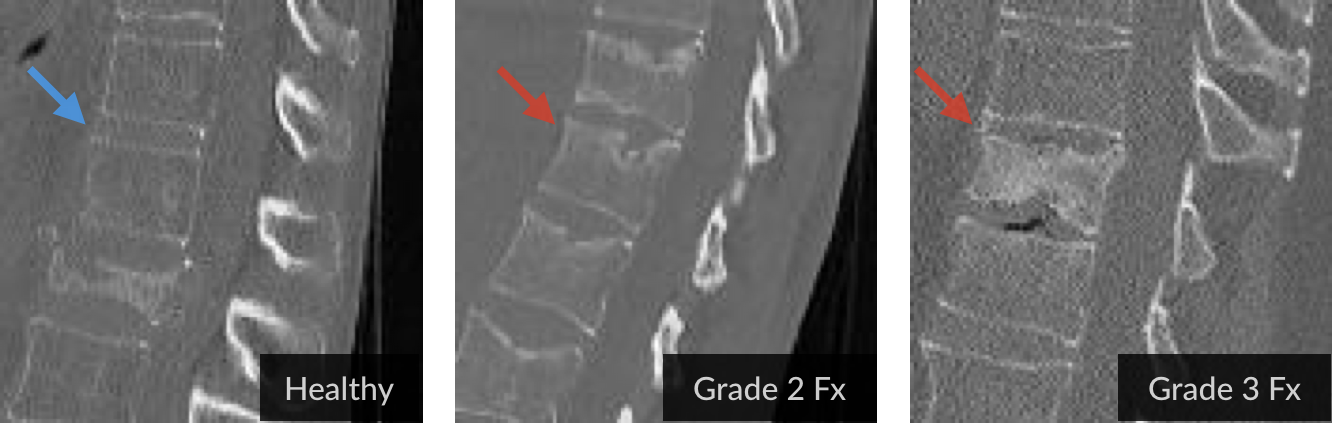

Figure 1: Illustrating fracture grades: (a) TSNE visualisation of latent representations learnt by formulating fracture detection as a simple classification problem, resulting in poor separability. (b) An example selection of the three classes of vertebrae studied in this work, healthy, grade-2 fracture, and grade-3 fracture.

Genant’s Vertebral Fracture Grading The Current gold standard in grading vertebral fractures is a semi-quantitative method developed by Genant et al [1], according to which fractures are categorized into three grades (Grades 1, 2, and 3; cf. Fig 1b). This is based on the height-loss a vertebra undergoes compared to its healthy counterpart. A healthy vertebra is considered to be Grade 0. Grades 2 and 3 have proven clinical consequences, while this is unknown for Grade 1; as its small height reduction results in a high inter-rater uncertainty, Grade 1 fractures are excluded in this study.